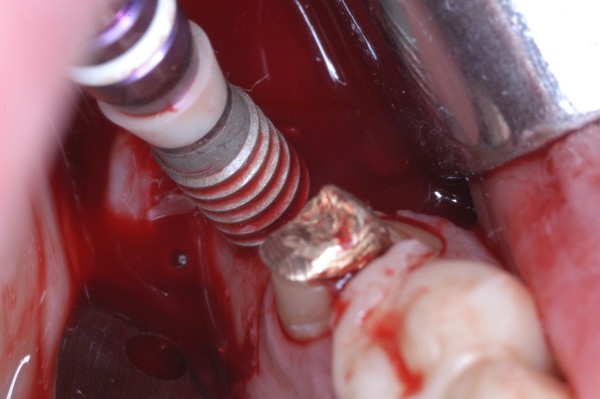

APRECIACIONES DIAGNÓSTICAS EN BASE A LA APERTURA MENTAL DEL CLÍNICO FRENTE A LO QUE EL PACIENTE PROPONE EN MUCHAS OCASIONES , LA DEMANDA DE LOS PACIENTES NOS INCLINAN A FOCALIZAR NUESTRA ATENCIÓN EN LAS PIEZAS DE LAS CUALES EL ENFERMO SE QUEJA. PACIENTE SEXO FEMENINO, 55 AÑOS, SE PRESENTA A LA CONSULTA DERIVADA POR COMPAÑERO GENERALISTA, QUIEN LLEVA MESES PROCEDIENDO A LA «DESINFECCIÓN» DE UN PRIMER PREMOLAR IZQUIERDO, EL QUE SE PRESENTA ABIERTO EN SU CONDUCTO EN EL AFÁN DE PERMITIR EL ESCAPE DE GASES DE UNA GANGRENA PULPAR. A LA INSPECCIÓN CLÍNICA SE OBSERVAN FACETAS PARAFUNCIONALES DE TERCER GRADO , ASINTOMÁTICAS, CON EVIDENTES DIFICULTADES MASTICATORIAS Y ESTÉTICAS , FALTA TOTAL DE SUS MOLARES INFERIORES, Y ADELANTAMIENTO PRONUNCIADO DE SU MANDIBULA, LA QUE CUESTA MANIPULAR DEBIDO A LA SITUACIÓN DE ESPASMO DE CASI TODA SU MUSCULATURA GNATICA. SE ESTUDIA EL CASO RADIOLOGICAMENTE, Y SE RELAJA EL SISTEMA MEDIANTE LAM. DE LONG REALIZANDO UN MONTAJE EN LA ORC OBTENIDA. NO SATISFECHOS CON EL RESULTADO, CONFECCIONAMOS UN JIG DE LUCIA, EL QUE DEJAMOS EN BOCA TODA UNA NOCHE, AL CABO DE LA CUAL REALIZAMOS UN NUEVO REGISTRO REALIZAMOS UN ENCERADO RÁPIDO DEL CASO, Y CONFECCIONAMOS UNA ESTRUCTURA OCLUSAL PLASTICA, QUE ADEMÁS REPONGA EL ASPECTO ESTÉTICO PERDIDO (FÉRULA DE RELAJACIÓN DE COMPONENTE ESTÉTICO), LO QUE PERMITE AL ENFERMO LUEGO DE DOS DÍAS DE USO, NO SOLO CORROBORAR LA COMODIDAD MASTICATORIA Y LA FALTA DE SÍNTOMAS MUSCULARES, SINO TAMBIÉN OBSERVAR APROXIMADAMENTE LA DIFERENCIA ENTRE LA SITUACIÓN INICIAL Y LO QUE PUEDE LOGRARSE MEDIANTE EL TRATAMIENTO. EL PACIENTE ADVIERTE LA MEJORÍA DE LA SITUACIÓN. ACEPTADO POR PARTE DEL MISMO EL TRATAMIENTO SUGERIDO, CREAMOS UN JUEGO COMPLETO DE PROVISORIOS EN BASE AL ENCERADO, Y PROCEDEMOS A TRATAR LA INFRAESTRUCTURA, QUE CONSISTE EN LAS ENDODONCIAS, SUS REFUERZOS A PERNOS DE ORO, LOS ASPECTOS PERIODONTALES DEL CASO, Y DOS IMPLANTES INFERIORES CON TÉCNICA SEMISUMERGIDA ,DE 5 MM DE ANCHO POR 12 DE LONGITUD, CON ANILLO DE ZIRCONIO , A LA ESPERA DE OSTEOINTEGRACIÓN, TRANSCURREN TRES MESES EN EL USO DE UNA NUEVA OCLUSIÓN CONSTITUIDA POR LOS PROVISIONALES, SEGÚN EL ENCERADO, QUE SE REALIZÓ SIGUIENDO LOS CÁNONES DE UNA OCLUSIÓN ORGÁNICA. COMPROBADA LA EFICACIA DE LA NUEVA SITUACIÓN, CON SUS DISCLUSIONES LATERALES Y POSTERO ANTERIORES CORRECTAS, CARECIENDO YA DE SINTOMATOLOGÍA MUSCULAR (SIN MIALGIAS, SIN MIOSITIS, Y CON UN GRADO DE APERTURA DE 4,50 CM), Y SIN SIGNOS EVIDENTES DE DESGASTE SOBRE EL MATERIAL DE LOS PROVISORIOS, ES DECIR: VERIFICANDO QUE EL PACIENTE YA NO BRUXA, VERTICALIZANDO EL CICLO MASTICATORIO /OTORGANDO ORC/ DIMENSIÓN VERTICAL /PROTEGIENDO A LAS PIEZAS `POSTERIORES DE IMPACTOS LATERALES RECIEN ENTONCES , MONTAMOS EN ARTICULADOR SEMI AJUSTABLE LOS MODELOS DE TRABAJO DEFINITIVOS. CONFECCIONAMOS ENTONCES LAS COFIAS INFRA PORCELANA, EN PORCELANA DE ALTA DENSIDAD EN EL SECTOR ANTERIOR Y EN ORO GALVÁNICO PARA EL SECTOR POSTERIOR PARA LUEGO COMPLETAR LA GUIA ANTERIOR , VERIFICANDO LA ALTURA DE LOS INFERIORES RESPECTO DEL LABIO INFERIOR Y CORROBORANDO LOS PUNTOS DE CONTACTOS INTER CANINOS, QUE CENTRALIZAN LA MANDIBULA Y VERTICALIZAN EL CICLO MASTICATORIO Y LAS DISCLUSIONES CANINAS QUE OTORGARÁN PROTECCIÓN A LOS SECTORES POSTERIORES. POSTERIORMENTE CHEQUEAMOS LA DISCLUSIÓN EN PROPULSIVA DE LA GUIA ANTERIOR YA TERMINADA. FIG38 FIG39 UNA VEZ OBTENIDO UN COMANDO ANTERIOR EFECTIVO, COMO LO ES LA GUIA ANTERIOR CON TODOS SUS COMPONENTES, PROCEDEMOS A REALIZAR LAS TABLAS PREMOLAR / MOLAR DE AMBOS LADOS Y OBSERVAMOS QUE LOS PUNTOS INTEROCLUSALES DE CONTACTO SEAN SUFICIENTES Y CUMPLAN SU OBJETIVO DE OTORGAR ESTABILIDAD MESIO DISTAL Y VESTÍBULO LINGUAL. TRANSCURRIDO UN AÑO DE FINALIZADO EL TRATAMIENTO, REALIZAMOS UN CHEQUEO POST OPERATORIO DEL CASO, EN TODOS LOS PARÁMETROS ANTERIORMENTE MENCIONADOS, Y OBSERVAMOS LA ABSOLUTA ESTABILIDAD DEL MISMO EN TODOS SUS NIVELES Y TEJIDOS.